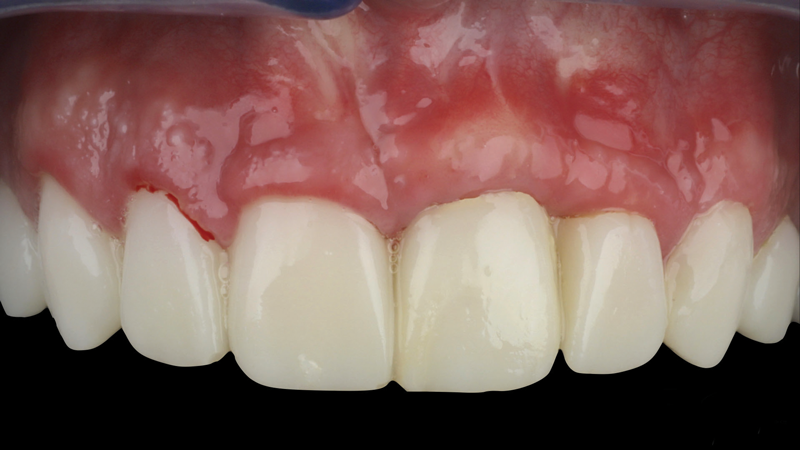

(9.) Postoperative photographs acquired after 2 weeks and 3 months of healing, respectively, demonstrating the reconstitution of an ideal tooth No. 9 marginal position in relation to its contralateral counterpart with increased soft-tissue thickness.

Figure 9

(10.) Postoperative photographs acquired after 2 weeks and 3 months of healing, respectively, demonstrating the reconstitution of an ideal tooth No. 9 marginal position in relation to its contralateral counterpart with increased soft-tissue thickness.

Figure 10

The patient in this case had undergone implant therapy at the site of tooth No. 9 and was restored with a cement-retained restoration more than 5 years prior. At presentation, the site demonstrated a peri-implant soft-tissue dehiscence that extended approximately 3-mm apical to the gingival margin of tooth No. 8. Thin and erythematous marginal tissue was evident at the zenith (Figure 2). The crown was removed, and a partial thickness flap was reflected using a papilla-sparing incision design. This revealed that the implant was positioned too far facially and that its body was visible through a very thin layer of bone (Figure 3 and Figure 4). The first objective of treatment was to minimize the facial extent of the emerging abutment and crown. To accomplish this, the facially positioned abutment and implant crown margin were both recontoured. The second treatment objective was to provide additional supracrestal soft tissue that would more adequately maintain the peri-implant margin. The tuberosity was selected as a donor site due to its dense, high-quality connective tissue, low propensity for shrinkage, and association with minimal patient discomfort. Once the graft was secured (Figure 5 through Figure 7), the flap was coronally positioned (Figure 8). After a healing period of 2 weeks, the margin of tooth No. 9 exhibited an ideal position in relation to its contralateral counterpart and demonstrated increased soft tissue thickness (Figure 9). Three months postoperatively, further healing had improved the esthetics and the position of the margin had been maintained (Figure 10).